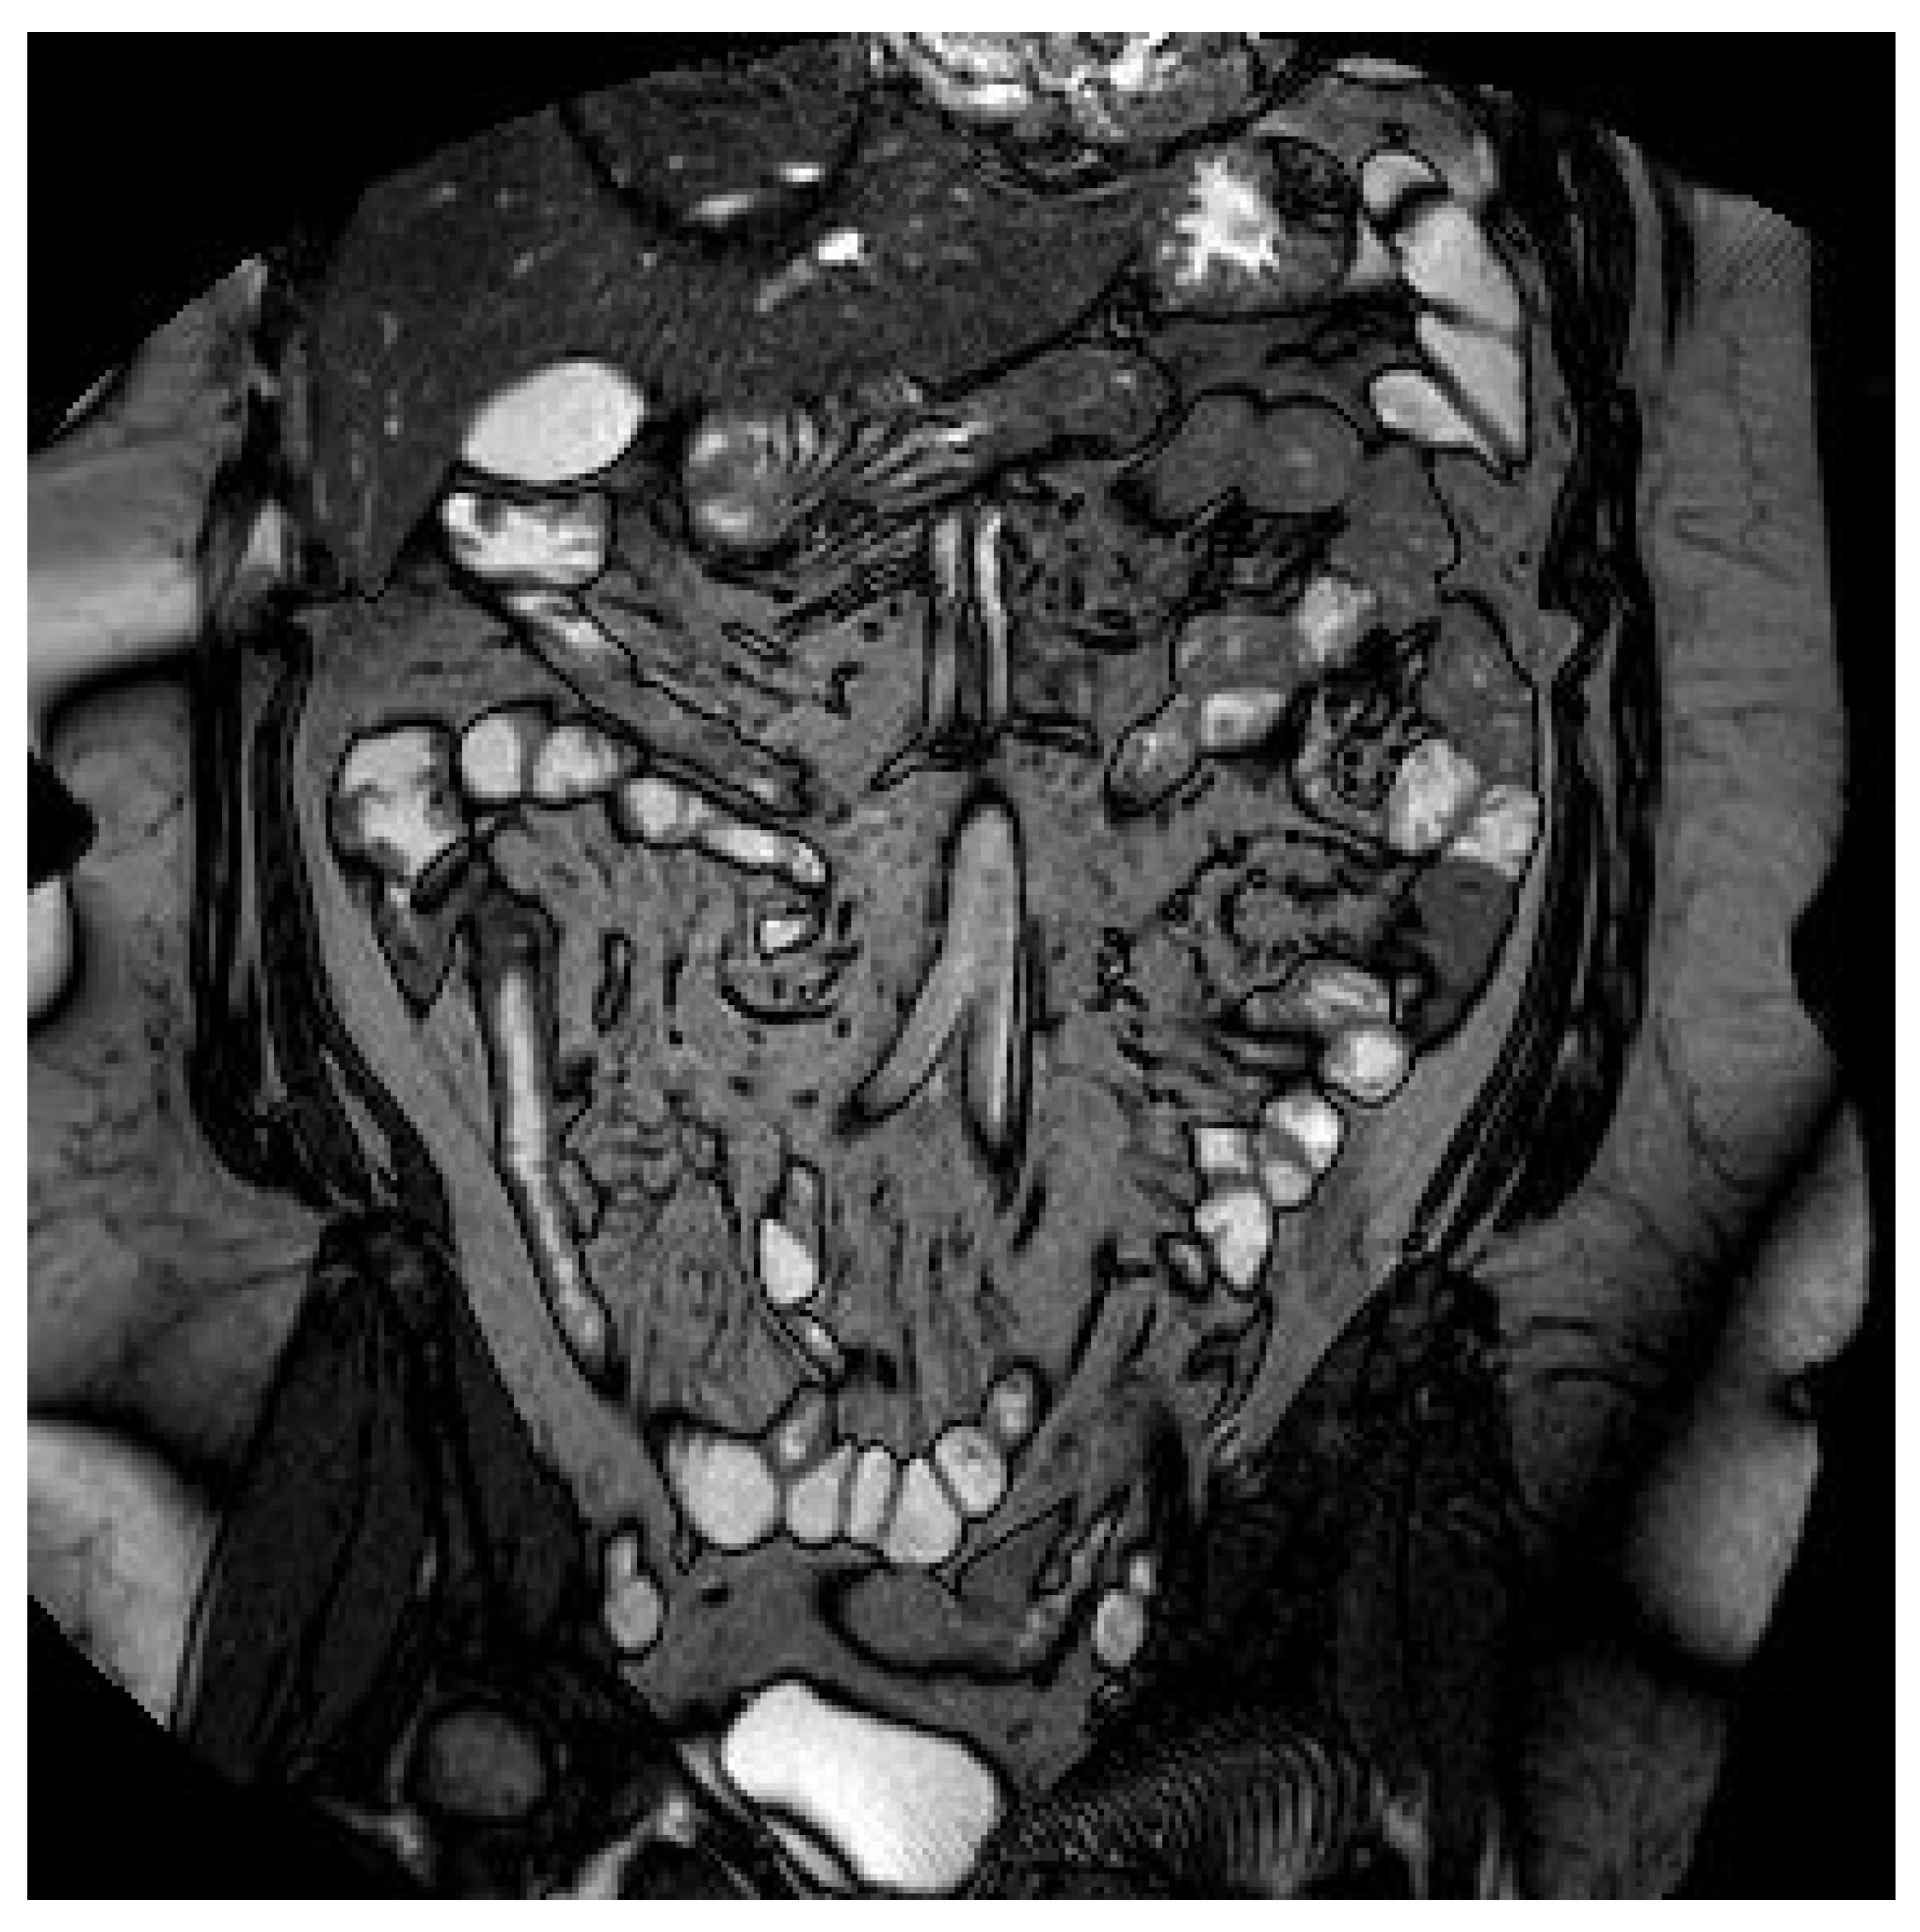

1.2. Case 2